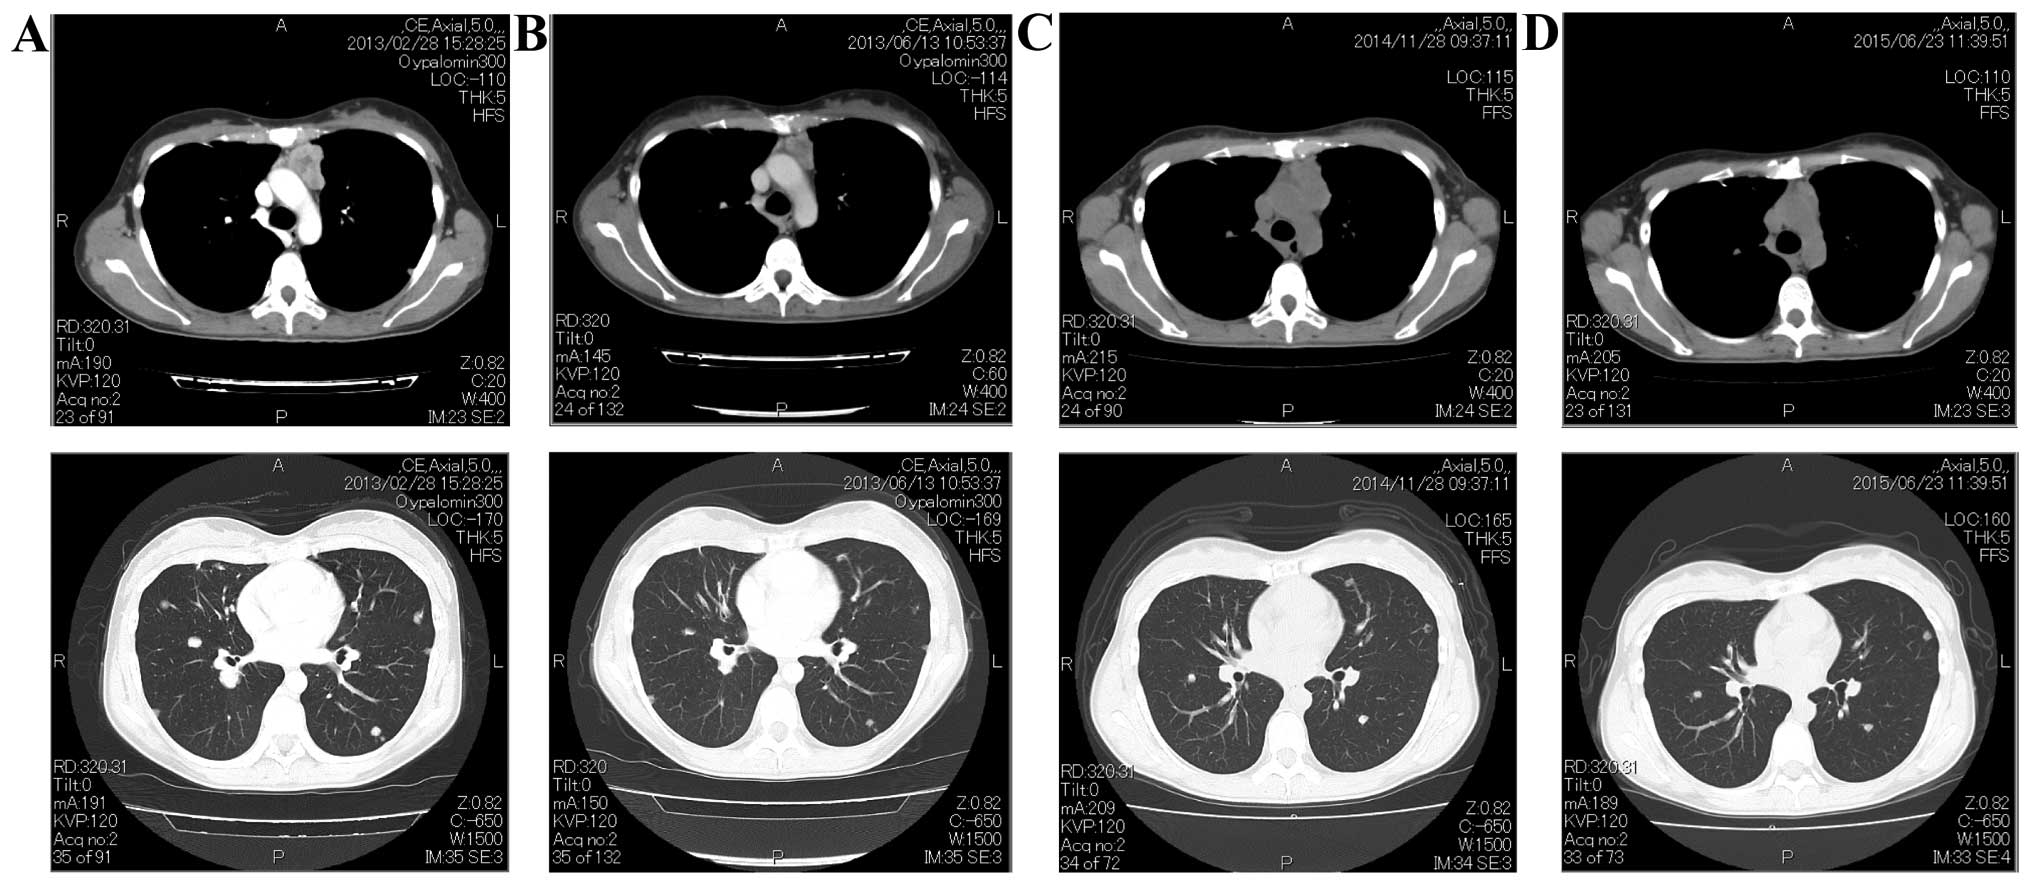

Rapid Response to Lenvatinib and Disease Flare After Discontinuation in Thymic Carcinoma Kit Mutation Kit mutations might enable targeted therapy. Guidelines are lacking for selection of the optimal treatment option for recurrent thymic carcinoma. Tet2, setd2, bap1, and asxl1 regulate epigenetics, suggesting disruption of these. Kit mutation is rare in thymic carcinoma, but so far the only known molecular. Thymic carcinomas featured a significantly higher frequency of alterations at 4.0/tumor (p <.0001). Mutations in. Thymic Carcinoma Kit Mutation.

Rapid Response to Lenvatinib and Disease Flare After Discontinuation in Thymic Carcinoma Kit Mutation Thymic carcinomas featured a significantly higher frequency of alterations at 4.0/tumor (p <.0001). Kit mutations might enable targeted therapy. Guidelines are lacking for selection of the optimal treatment option for recurrent thymic carcinoma. Kit mutation is rare in thymic carcinoma, but so far the only known molecular. Mutations in the kit gene have been related to response to imatinib in. Thymic Carcinoma Kit Mutation.